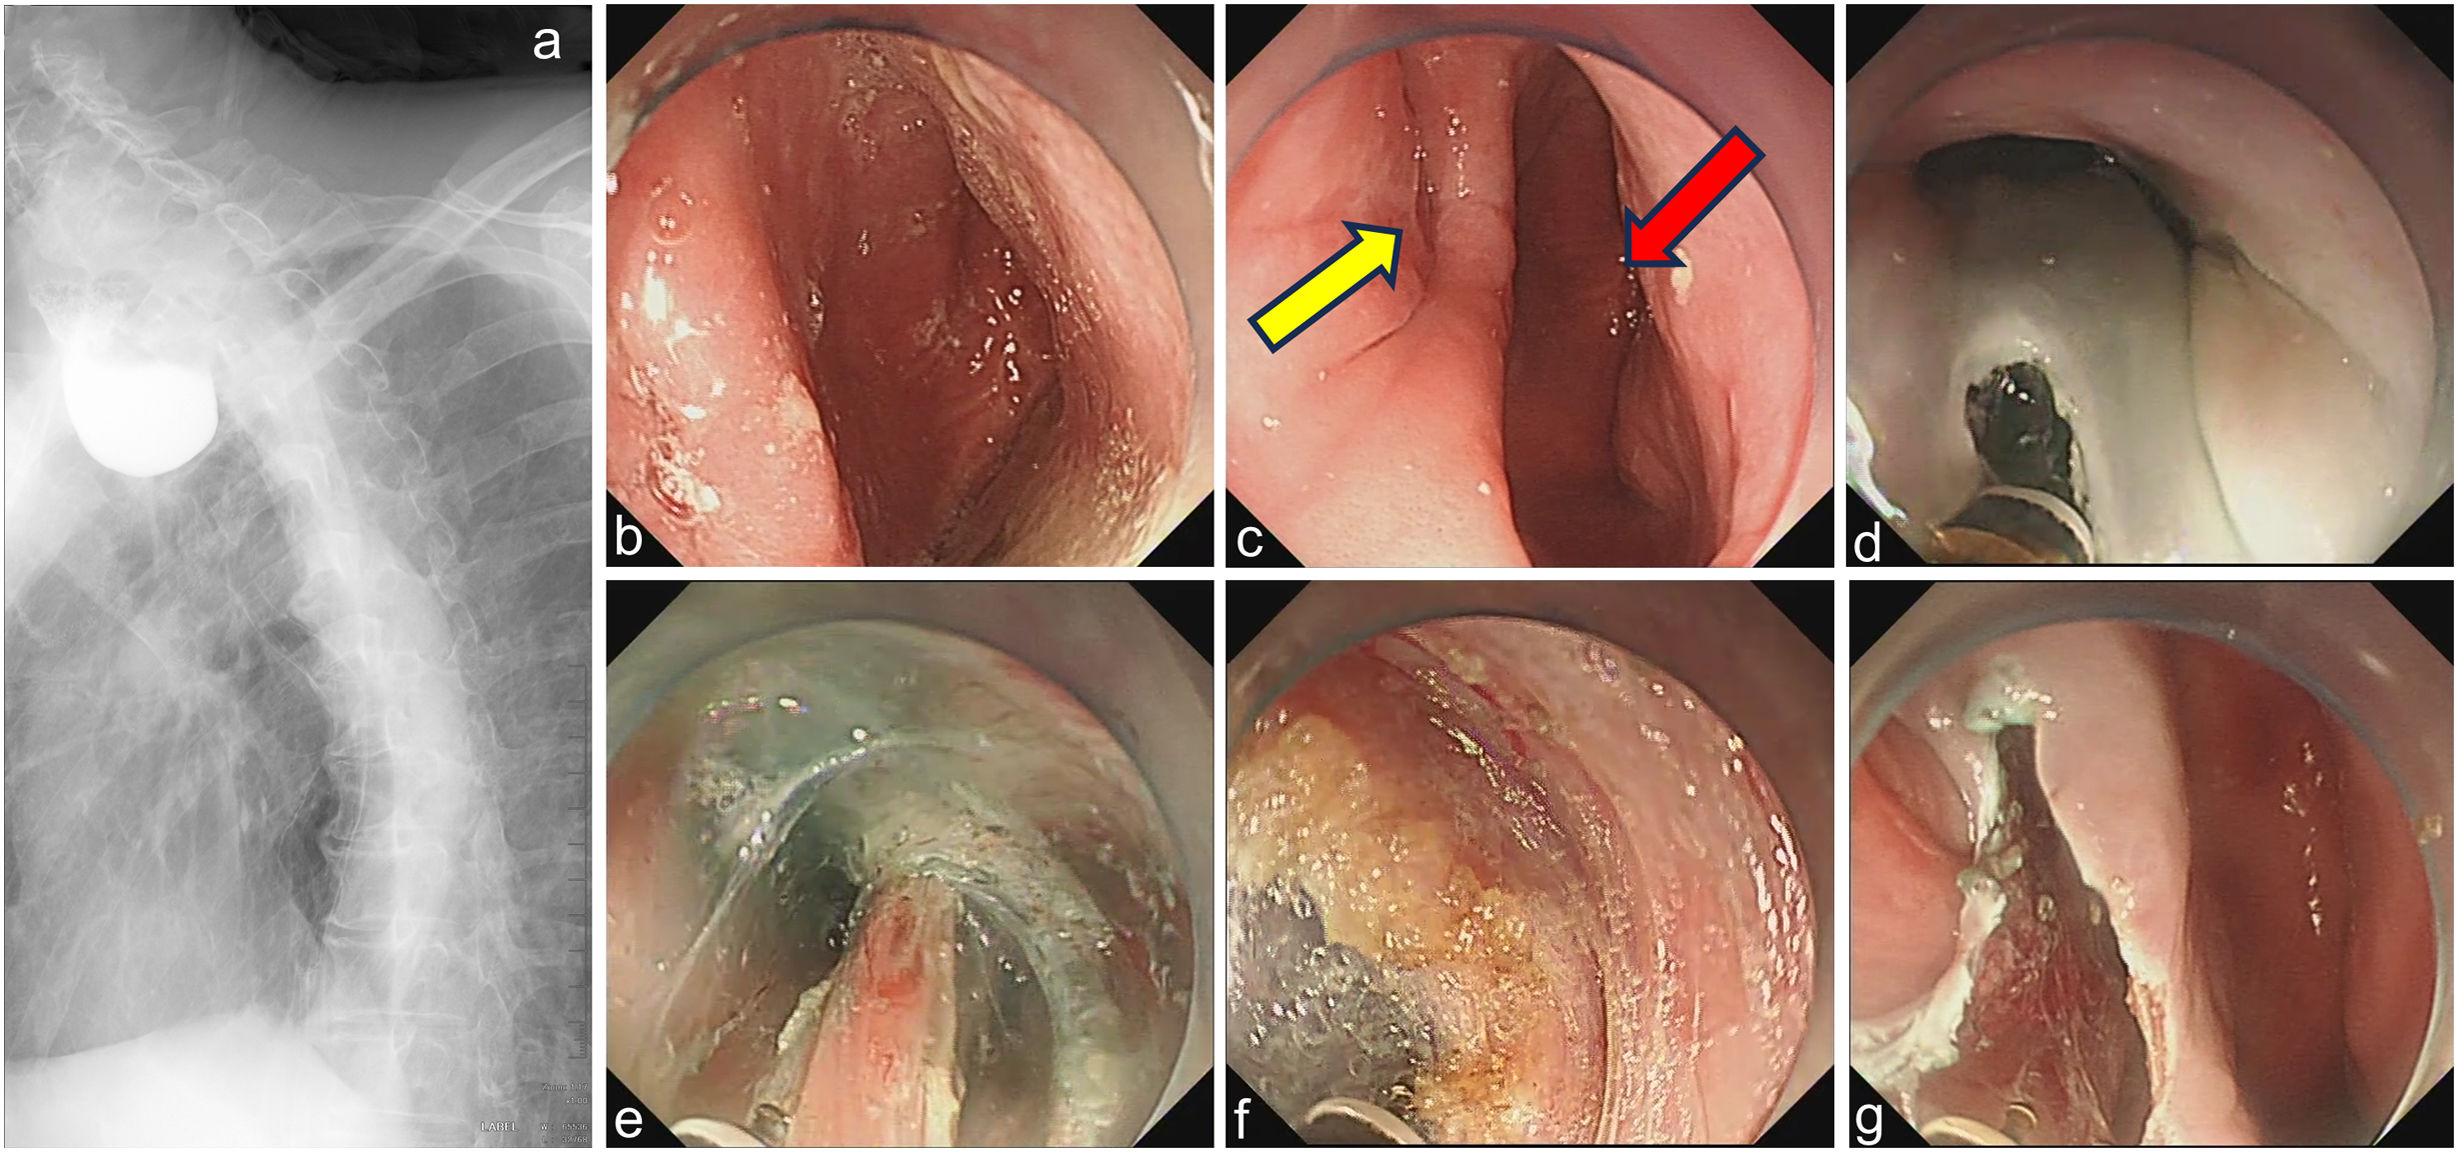

An 84-year-old male with decadal dysphagia demonstrated a large Zenker's diverticulum harboring food debris on endoscopy (Fig. 1a–c). Z-POEM was performed with luminal debridement, followed by mucosotomy, submucosal tunneling, and complete cricopharyngeal myotomy (Fig. 1d–f). Critical intraoperative finding: a large residual mucosal septum – a documented recurrence risk factor1 – persistently obstructing the lumen (Fig. 1g).

Esophagram and standard Z-POEM. (a) Large Zenker's diverticulum; (b) food debris retention within the diverticular sac; (c) luminal view after debridement (yellow arrow: true esophageal lumen; red arrow: diverticular orifice); (d) mucosal incision initiated 2cm proximal to the septal base; (e) bilateral submucosal tunneling along the septum; (f) completed cricopharyngeal myotomy; (g) residual mucosal septum obstructing the true lumen (asterisk).